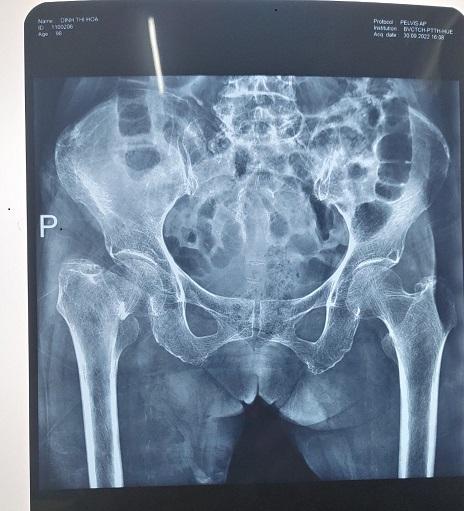

XQ: gãy cổ xương đùi phải

Chẩn đoán : Gãy cổ xương đùi phải/ Máy tạo nhịp tim

Hình ảnh : Phim XQ trước và sau mổ thay khớp háng phải.